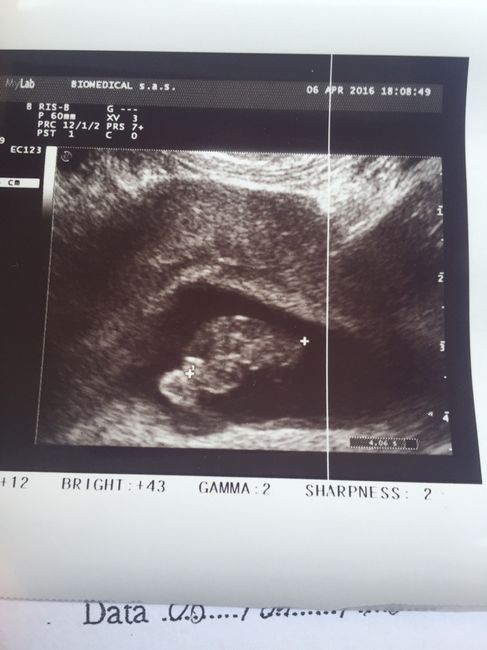

Oggi prima ecografie ecco a voi il mio fagiolino/a a 7+4.1,6cm d amore.....